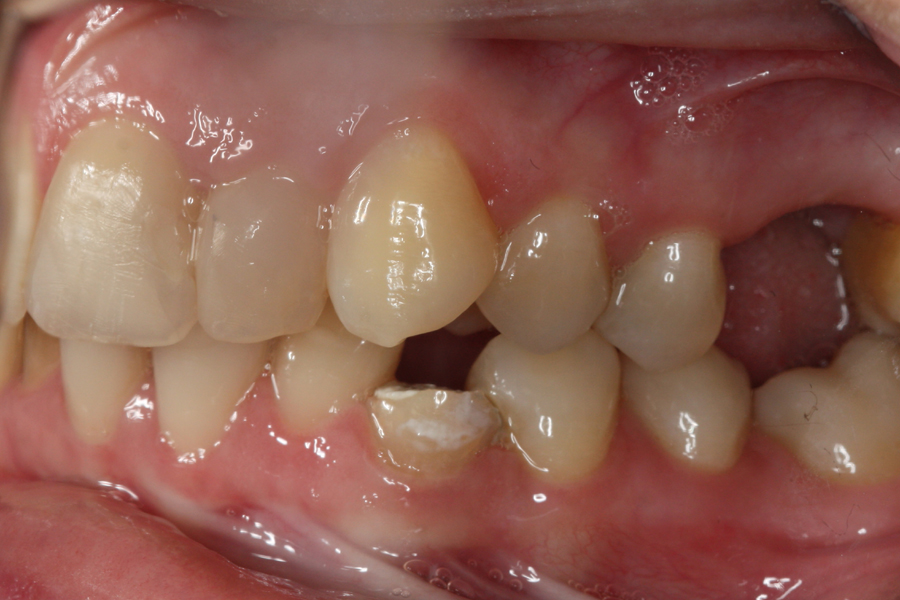

Młoda pacjentka zgłosiła się do naszego gabinetu celem wykonania kompleksowego leczenia zachowawczo-ortodontycznego. Oprócz problemów natury ortodontycznej stwierdzono złą higienę jamy ustnej oraz liczne potrzeby leczenia zachowawczo-endodontycznego. Po wnikliwej analizie telerentgenowskiej oraz analizie modeli zadecydowano o ekstrakcji 2 zębów w łuku dolnym (kła po stronie lewej oraz pierwszego przedtrzonowca po stronie prawej). Plan leczenia obejmował ponadto zamknięcie łuku po brakujących zębach w łuku górnym. Leczenie aktywne trwało 2 lata i 8 miesięcy. W czasie jego trwania pacjentka była regularnie poddawana zabiegom higieny profesjonalnej celem eliminacji zapaleń przyzębia brzeżnego. Po leczeniu aktywnym zastosowano leczenie retencyjne w postaci retainera stałego w żuchwie oraz szyny retencyjnej w łuku górnym.